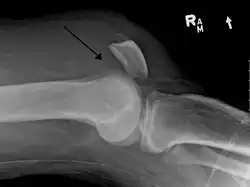

![]() | |

An x-ray demonstrating quadriceps tendon rupture. Note the abnormal angle of the patella and soft-tissue swelling marked by the arrow. | |